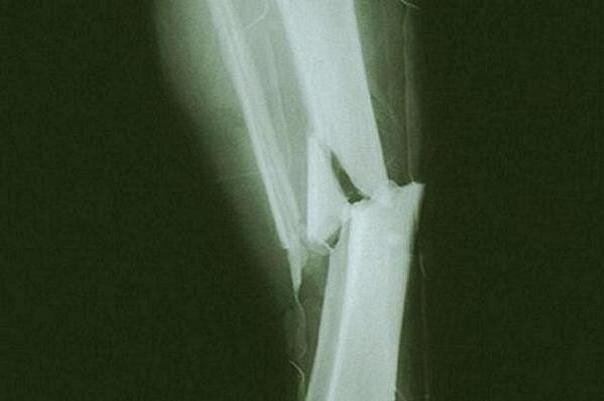

ایسنا: پوکی استخوان با از دست دادن توده استخوانی و تخریب ریزساختار استخوان مشخص میشود و استخوانها را شکننده و آسیبپذیر میکند و خطر شکستگی را افزایش میدهد.

یافتههای یک تحقیق نشان داد که سطوح بالای سرب خون با کاهش تراکم استخوان در ستون فقرات کمر، لگن و کل استخوان ران زنان مرتبط است. از سوی دیگر، افزایش سطح سلنیوم خون با افزایش تراکم استخوان در لگن مرتبط است. هیچ ارتباطی برای سایر عناصر کمیاب مانند آهن، روی، مس، منگنز، کادمیوم یا جیوه یافت نشد. محققان همچنین پیشنهاد کردند که افزایش سطح سرب خون ممکن است خطر پوکی استخوان را در زنان افزایش دهد، در حالی که سایر عناصر کمیاب چنین تأثیری ندارند.

از یافتههای کلیدی حاصل از تحقیق، محققان دریافتند که سطوح بالای سرب خون با کاهش تراکم استخوان در ستون فقرات کمری، لگن و کل استخوان ران در زنان مرتبط است. سطوح بالاتر سلنیوم خون با افزایش تراکم مواد معدنی استخوان لگن در زنان مرتبط بود. هیچ ارتباط خطی بین تراکم مواد معدنی استخوان و سایر عناصر کمیاب خون وجود نداشت. ارتباط بین سطوح سرب، شیوع تراکم پایین مواد معدنی استخوان و شیوع پوکی استخوان معنا دار بود و هیچ ارتباطی بین سایر عناصر کمیاب خون و تراکم پایین مواد معدنی استخوان یا پوکی استخوان مشاهده نشد.